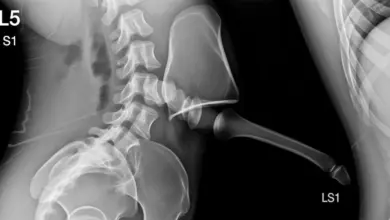

- Radiografias em AP, perfil e odontoide, para mapear níveis fundidos e curvaturas.

- Tomografia, quando é preciso detalhar anatomia óssea pré-operatória.